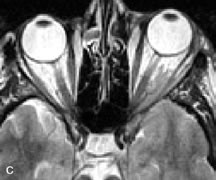

Extraocular muscle enlargement in patients with thyroid-associated orbitopathy is demonstrated equally well with CT and MRI studies. However, the superior tissue contrast on MR images reveals better details of the relationships of the optic nerve to the thickened muscles at the orbital apex (Fig. 16).50 In addition, MRI may be able to differentiate between muscles that are enlarged as a result of edema and active inflammation and those enlarged because of fibrosis by their T2 relaxation times.21 Quantitative MRI was not found to be accurate in predicting the success of low-dose orbital irradiation.51 However, a muscular index relating the diameters of the rectus muscles to the bony orbital dimensions was useful in predicting optic nerve compression.52

Fig. 16. A-C, T1-weighted MR scans obtained with a high-resolution surface coil demonstrate fusiform enlargement of the extraocular muscles. The medial, lateral, and inferior rectus muscles are especially involved. Note the relative sparing of the tendinous insertions, a finding characteristic of this disease process, as well as fatty infiltration of the lateral and inferior rectus muscles. There is marked proptosis, best visualized on the sagittal image (A), and mild crowding of the optic nerve at the orbital apex.